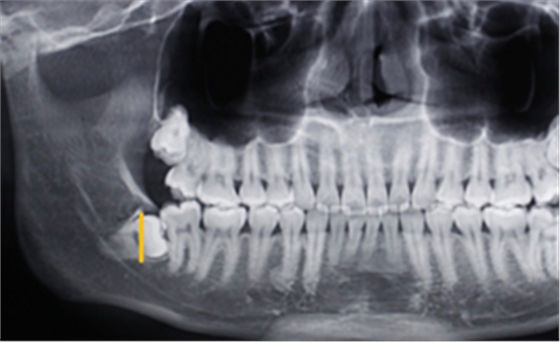

第一:確定阻力去骨的范圍:

第二:充分暴露牙體組織后,沿47牙長(zhǎng)軸方向?qū)?8進(jìn)行分冠,分冠線如下:

第三:分冠后近中牙體組織若無(wú)法順利脫位,可進(jìn)一步將近中牙冠分為頰舌兩部分,依次脫位。